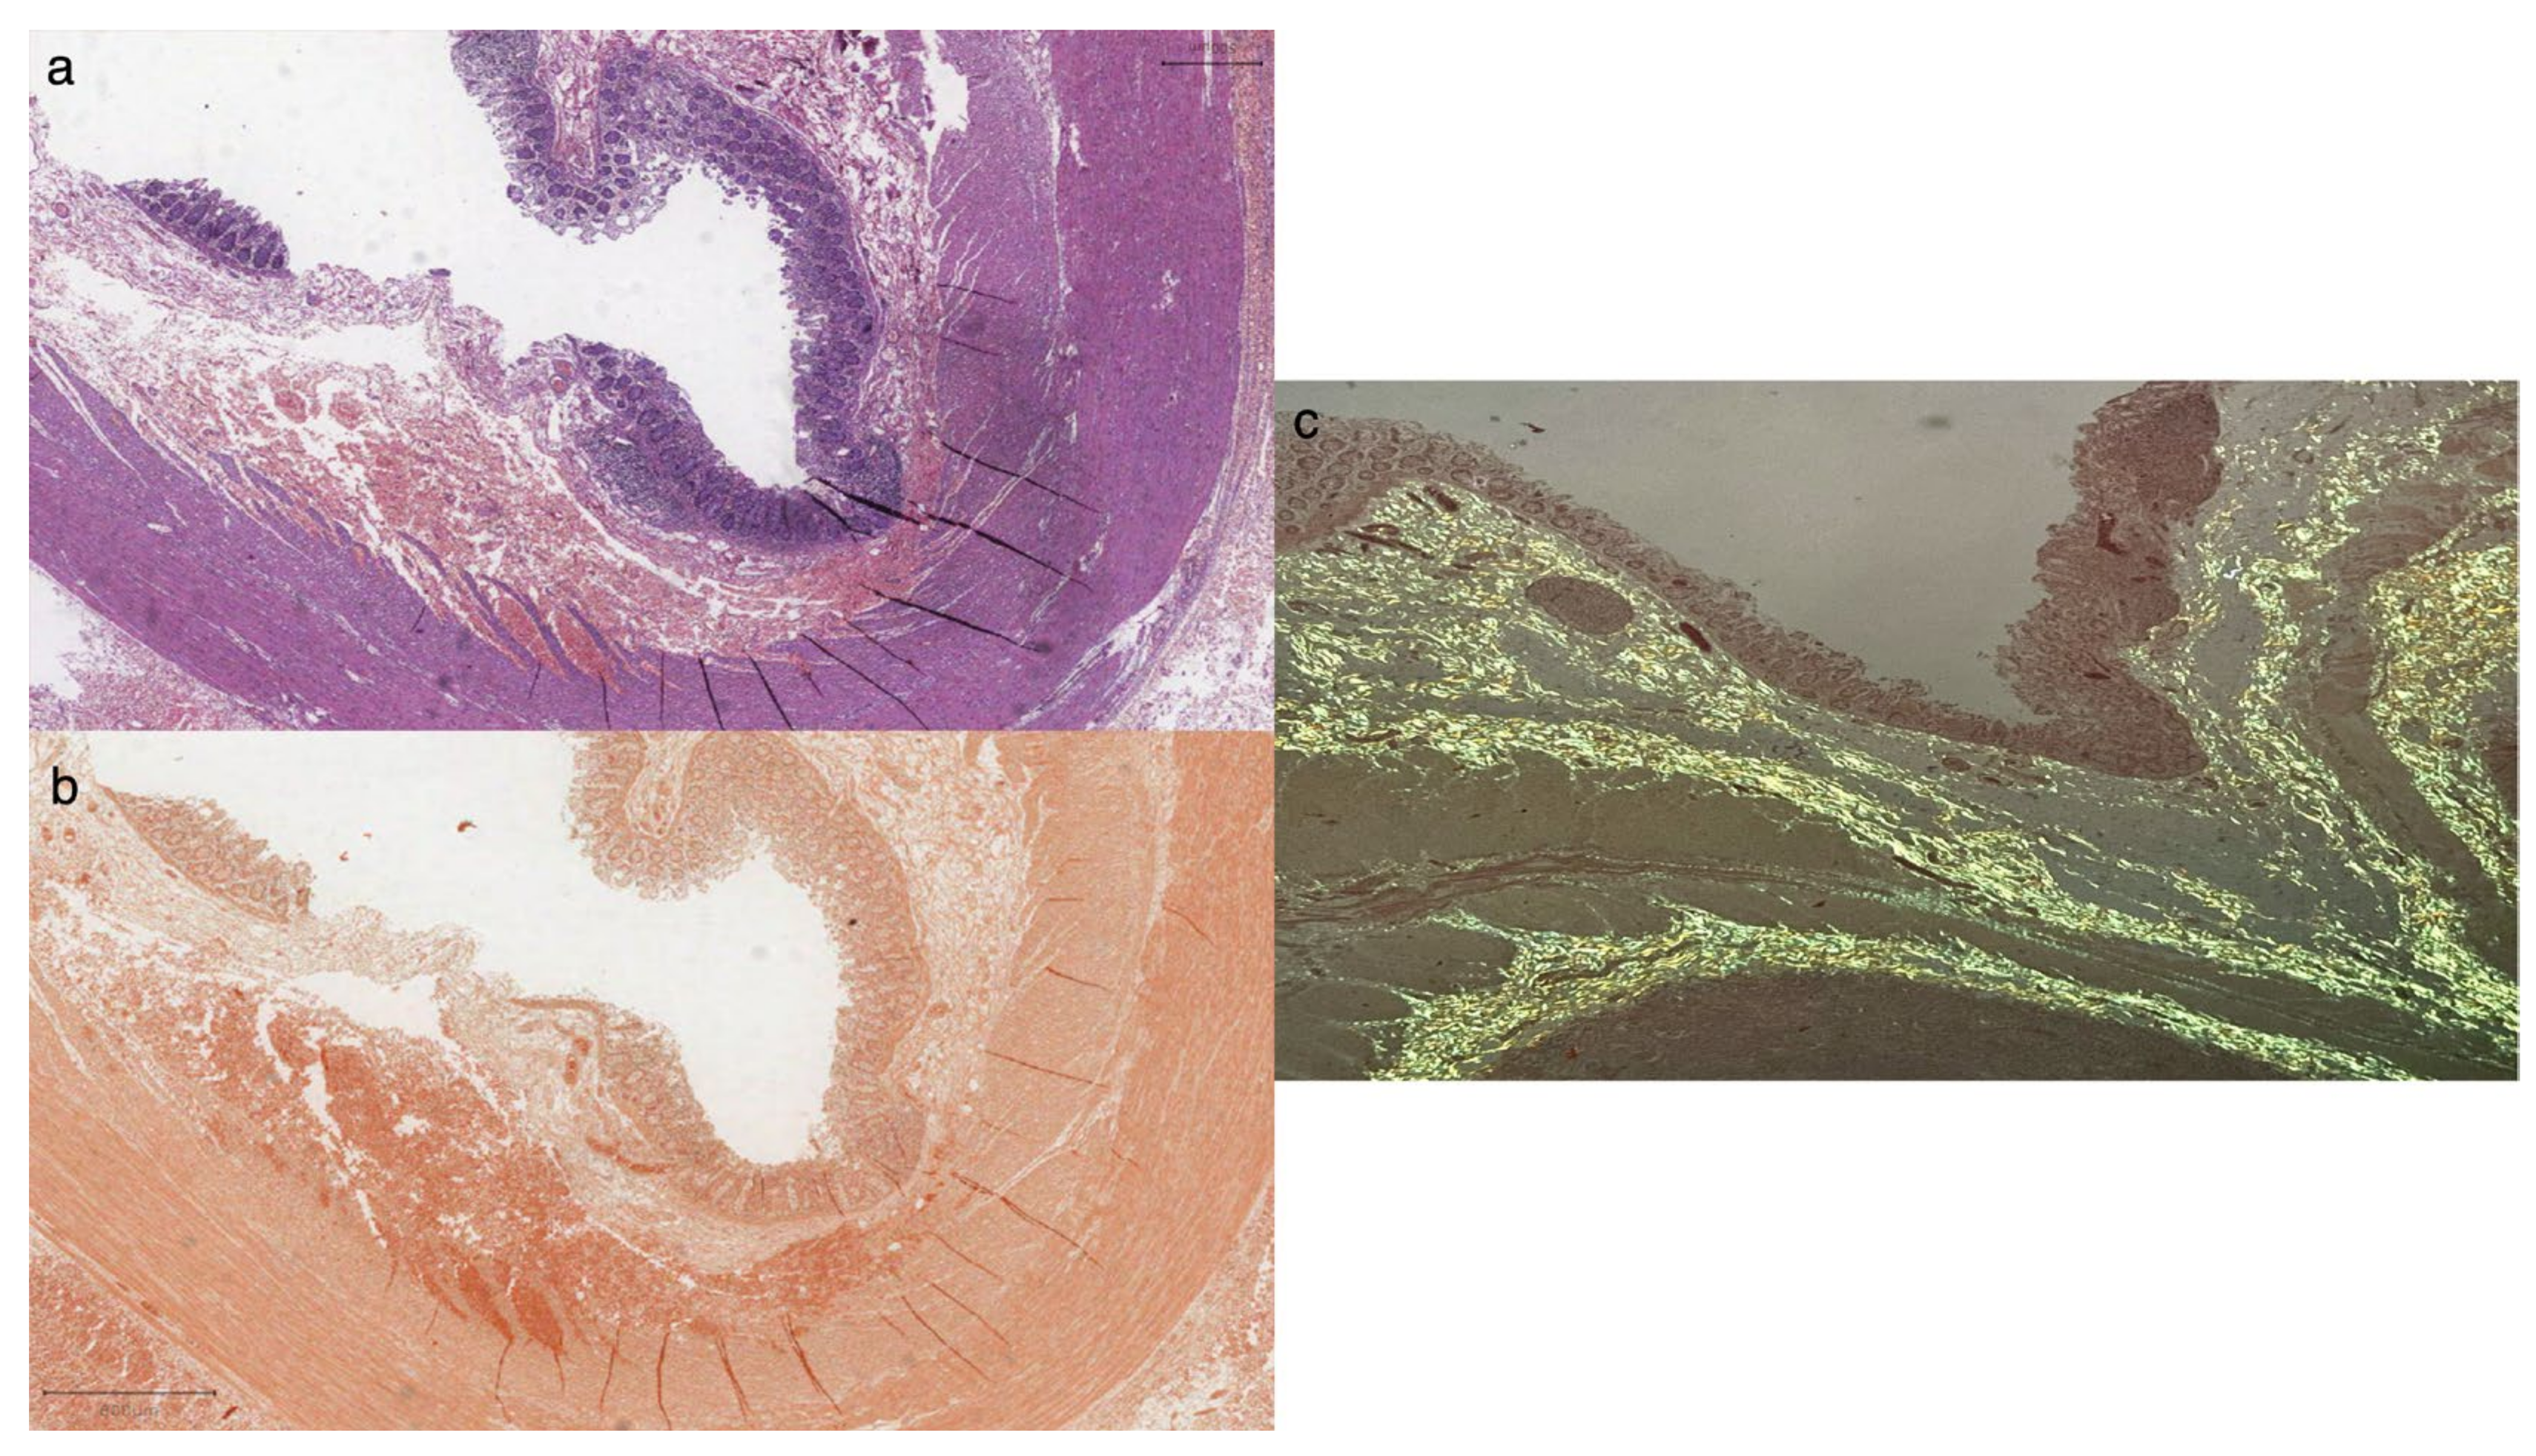

2. Case Presentation